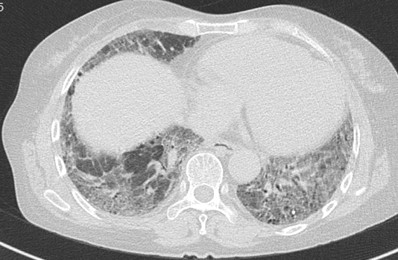

病例2:患者,女,59歲,因“反復(fù)咳嗽、咳痰、氣促8年余”于2024年7月12日求診我院?;颊叨嗄陙矸磸?fù)就診多家醫(yī)院,始終無果。入住我院后經(jīng)多學(xué)科會(huì)診,確診由微生物引起的纖維化型過敏性肺炎。原來患者從事香菇種植工作,歷經(jīng)8年,終于揪出幕后真兇。

病例3:患者,女,73歲,因“咳嗽、氣促5月余”于2024年7月8日求診我院,后確診纖維化型過敏性肺炎,經(jīng)反復(fù)詢問病史和生活情況,過敏原是患者長(zhǎng)期蓋的羽絨被。

病例4:患者,女,75歲,因“咳嗽、咳痰、氣促10余天”于2024年6月25日求診我院,后確診過敏性肺炎,過敏原是患者家中花園里種的各種花花草草。

過敏原無處不在,但又很隱匿,宿主的易感性也不一樣。過敏性肺炎早發(fā)現(xiàn)、脫離環(huán)境就可以治愈,但是由于患者經(jīng)常未及時(shí)發(fā)現(xiàn)過敏原,對(duì)于早期肺部比較典型的影像特征也缺乏足夠的敏感性,仍繼續(xù)暴露在過敏環(huán)境中,最后發(fā)展成纖維化型過敏性肺炎。我院間質(zhì)肺規(guī)范化診療中心將盡可能詳盡地采集病史以發(fā)現(xiàn)可能存在的環(huán)境暴露因素以及時(shí)間軸關(guān)系,發(fā)揮多學(xué)科診療優(yōu)勢(shì),早發(fā)現(xiàn)早診斷,助力患者盡快脫離過敏原,避免不可逆的肺纖維化。